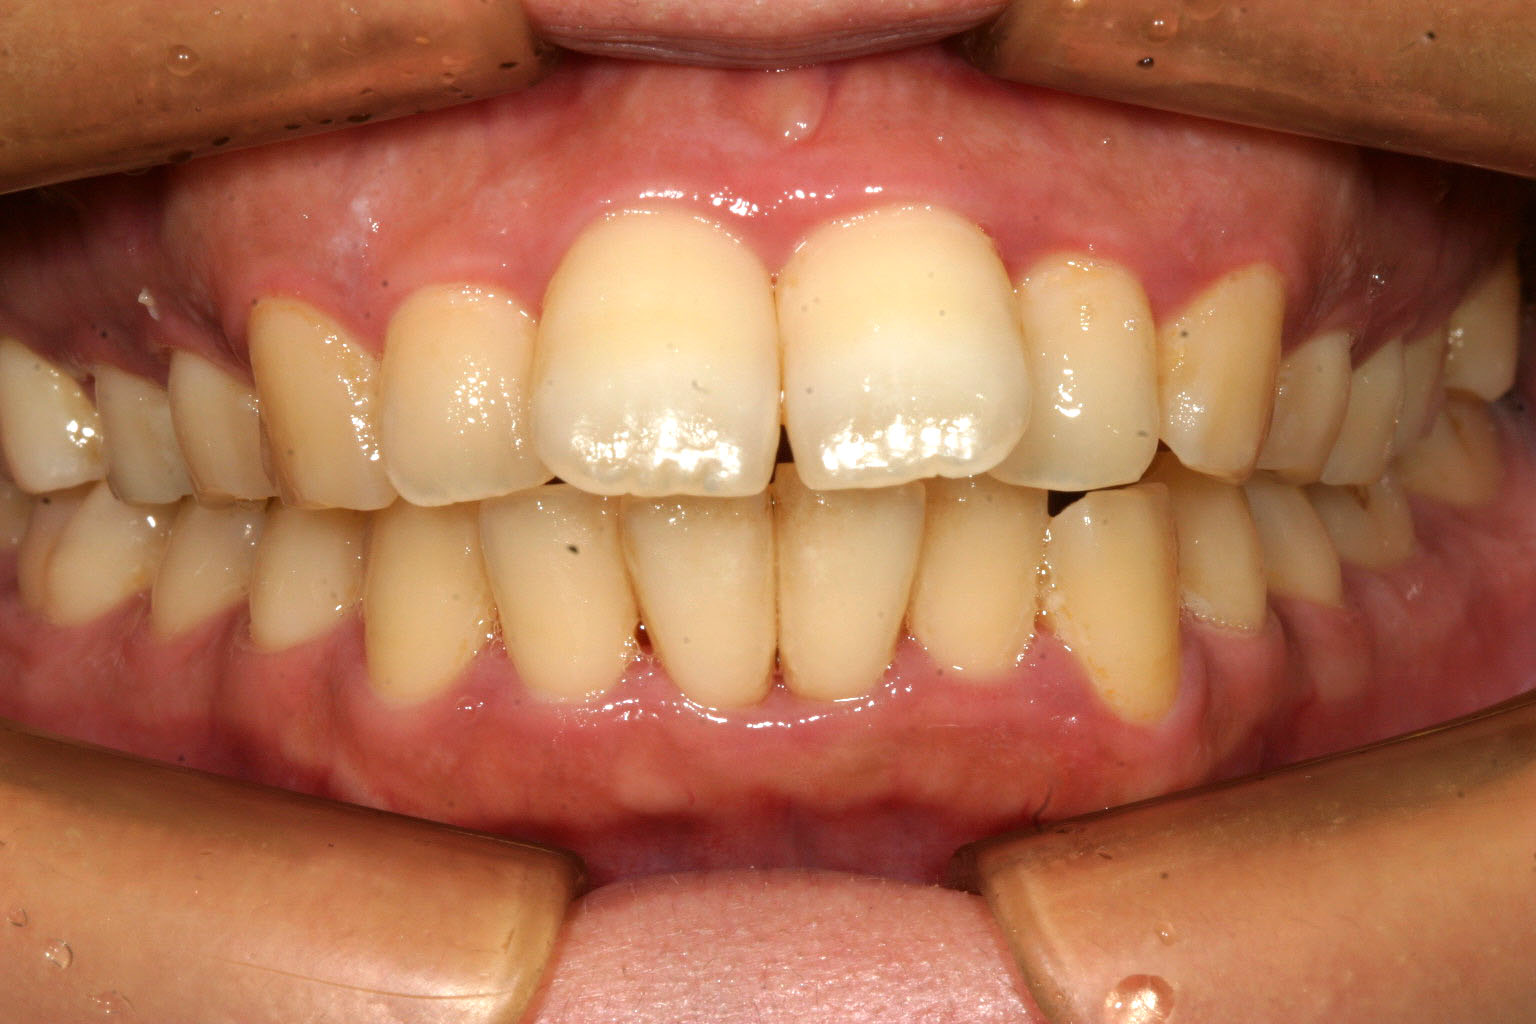

アーチが狭いお陰で前歯が前突しています。

下顎にも少し叢生が見られます。

側面観は少し出っ歯が目立ちます。